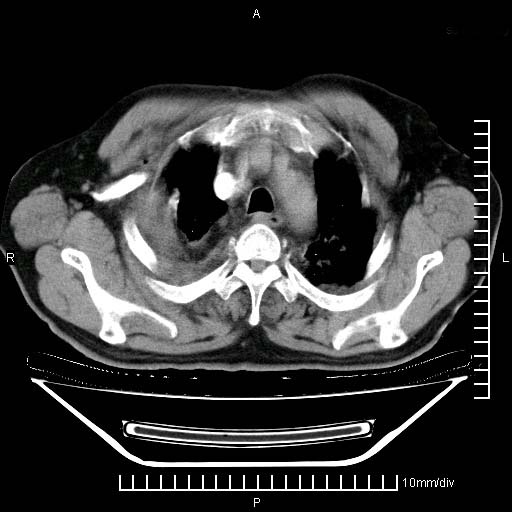

既往肺结核,近10几天,咳嗽,咳痰,右侧胸痛,疼痛较明显,右上肺斑块考虑结核灶胸膜粘连,增强,可惜动脉期没有定好,未见强化,可延迟4分后又见较明显强化,中心见低密度影,如果说结核是边缘强化,可这个灶强化的面积挺大的,让人很挠头。

延迟4分后